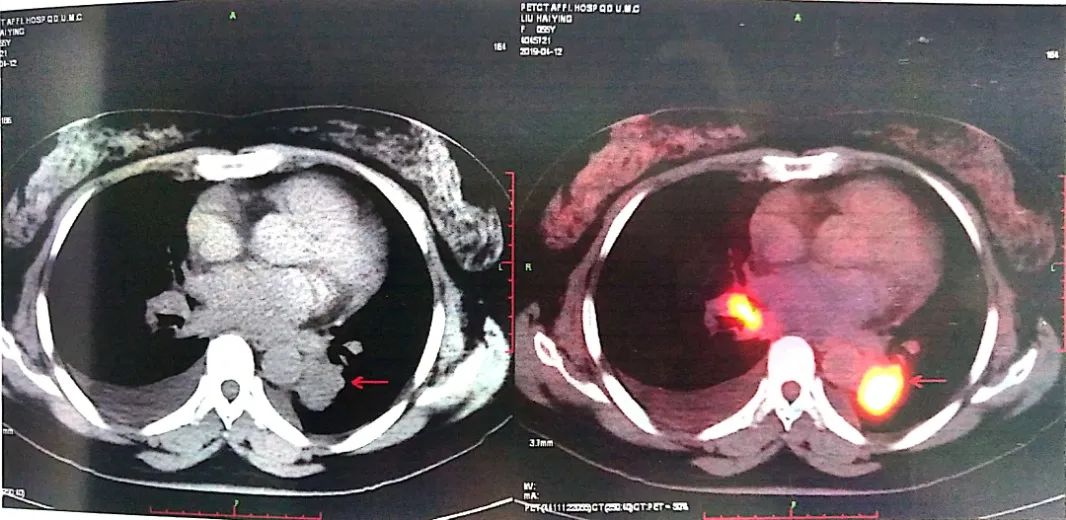

至此为止,患者的诊断为:肺恶性肿瘤 小细胞癌 广泛期 cT4N3M0 IIIC期(病灶1:右肺下叶,病灶2:左肺下叶),此时先给予标准化疗方案,EP方案:依托泊苷100mg/㎡ d1-3+顺铂75mg/㎡ d1-2 q21d*2。结果如下:

可以看到右肺下叶的病灶有明显缩退,但左肺下叶情况未能改善,因此我们再次在CT引导下左肺占位穿刺活检术。在给予第3周期EP方案化疗方案的同时,进行病理检测,发现理:左下肺病灶为低分化癌,符合腺癌,不除外复合性癌可能。通过肺癌常见基因检测(ARMS法)确定为ALK融合阳性。

而结合2012年胸外科杂志上的一篇关于《小细胞肺癌合并exon.19缺失以及ALK+案例报道》,我们倾向于患者为双肺双原发。

也因此我们修改诊断为,右肺下叶小细胞癌 局限期 cT2aN3M0 IIIB期以及肺下叶腺癌 cT4N2M0 IIIB期 ALK基因融合。